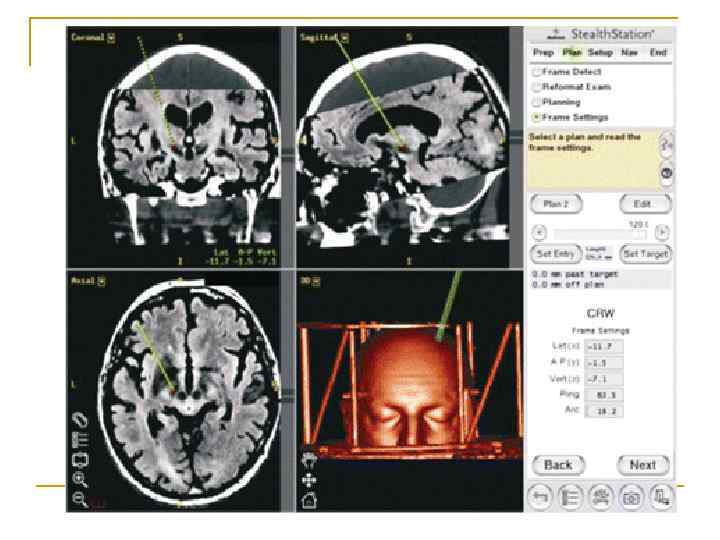

Стереотаксис n n n Метод определения точной локализации структур головного и спинного мозга Он используется как в экспериментальных исследованиях, проводимых на низших организмах, так и в некоторых нейрохирургических процедурах, выполняемых на людях. Метод стереотаксиса позволяет перемещать инструмент (например, электрод для регистрации электрической активности нервной ткани), руководствуясь особенностями черепа и подробным, трехмерным атласом мозга данного вида.

Вопрос 1. 8 Стереотаксис Физиология человека Под редакцией В. М. Покровского, Г. Ф. Коротько Медицина, 2003 (2007) г. Страница 97 -98.

Стереотаксис n n от греч. stereos – объёмный, пространственный и taxis – расположение, движение совокупность приёмов, позволяющая с помощью специальных приборов и методов визуализации и функционального контроля с большой точностью осуществить доступ в определённую структуру головного мозга.

Стереотаксис n n Ранее расчёты доступа к точке-мишени производились по краниальным и косвенно визуализируемым внутримозговым точкамориентирам с применением стереотаксических атласов (Spiegel, Wycis, Talairach, Shaltenbrand). При этом подразумевалось наличие нормального, анатомически неизменённого мозга пациента.

Стереотаксис n Сейчас стереотаксические системы с компьютеризированными средствами обеспечения расчётов, позволяющих планировать доступ к точке-цели по КТ-, МРТ, ПЭТ- изображениям мозга конкретного пациента.

Стереотаксис

Стереотаксическая хирургия n является малоинвазивным методом хирургического вмешательства, когда доступ осуществляется к целевой точке внутри тела или толщи тканей какого-либо органа с использованием пространственной схемы по заранее рассчитанным координатам по трехмерной Декартовой системе координат.

Стереотаксис n Биопсия мозга при помощи стереотаксиса. Маленькая часть опухоли взята через иглу вакуумной системы. Рамка вокруг головы пациента гарантирует правильное направление к цели (макс. ошибка : ~1 мм).